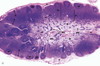

A

MALT

mucosa associated lymphoid tissue